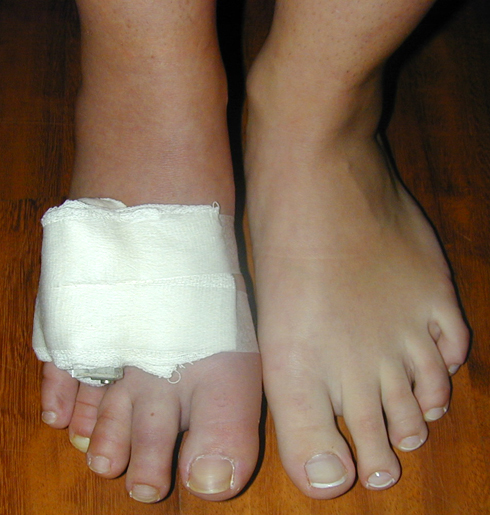

Metakarp kısalığında kozmetik görünümün bozulması ve dominant elin kullanımı sırasında yorulma, metatars kısalığında ise kozmetik haricinde metatarsalji, kısa parmağın dorsale kayması sonucu deformite oluşması, plantar yönde açılanması sonucu ağrı ve bası ülserleri, ve ayakkabı giymede zorluk nedeniyle ameliyat gerekebilir.